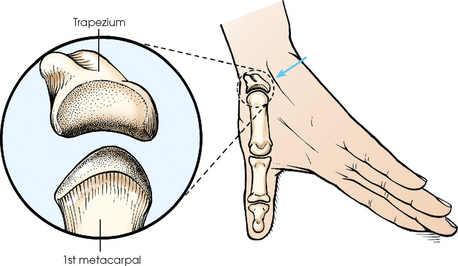

Robert1 first described the radiographic projection of the first CMC joint in 1936. Lewis2 modified the central ray for this projection in 1988, and Long and Rafert3 further modified the central ray in 1995. This projection is commonly performed to show arthritic changes, fractures, displacement of the first CMC joint, and Bennett fracture. The Robert method does not replace the initial AP or PA thumb projection.

Fig. 4-46 Hyperextended hand and thumb position for AP projection of first CMC joint: Robert method. Soft tissue of palm (arrow) is positioned out of the way so that joint is clearly shown. Inset: First CMC joint is a saddle joint; articular surfaces are shown.

Structures shown: This projection shows the first CMC joint free of superimposition of the soft tissues of the hand (Fig. 4-48).

When hyperextension of the wrist is not contraindicated, Burman1 stated that this projection provides a clearer image of the first CMC joint than the standard AP projection.